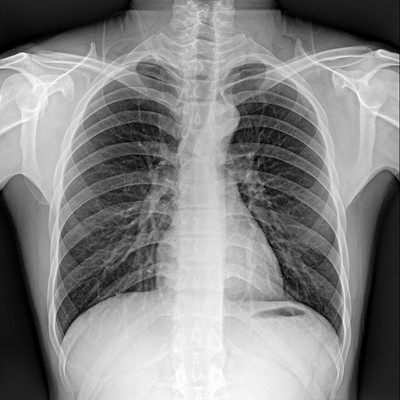

高品質影像鏈 讓您看的更清晰 PLX8500C/D

●大尺寸非晶硅平板探測器。

●非晶硅平板探測器,采用先進的制造工藝、性能更穩定。

●探測器可以大范圍轉動,大尺寸有效探測面積,可滿足人體多部位攝影需求。